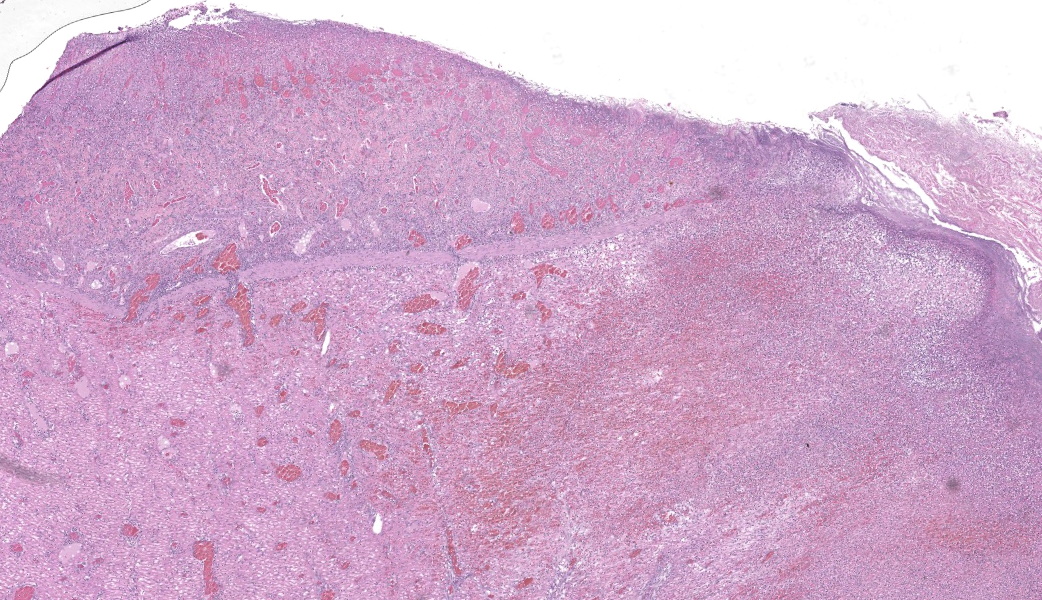

Findings are very similar in all cases that were submitted to the diagnostic laboratory.In all samples from the grossly discolored and swollen segment there was transmural necrosis of the intestine with extensive hemorrhage extending into the mesenteric fat. In the adjacent viable intestine there was eosinophilic infiltration of variable intensity. There was multifocal necrosis of mesenteric fat and, in some sections, diffuse eosinophilic infiltration. Large vessels were dilated and many contained thrombi.

Acute transmural necrotizing eosinophilic enteritis and eosinophilic peritonitis with arterial mesenteric thrombi and rare intralesional nematode larvae (spirurid)Contributor's Comment:

Several cases of this condition were diagnosed in the last few years in Israel, where incidence of Spirocerca infection is high.1,7 We have not observed breed or age predilection. The presenting history is usually that of intestinal infarction, with or without peritonitis. Clinical DDs are volvulus or intussusception.Heavy eosinophilic infiltration of mesenteric fat and thrombi are a common histologic finding in all samples in addition to acute transmural intestinal necrosis. In only a few of the samples intralesional larvae have been observed.

- Mesentery: Arteritis and periarteritis, necrotizing and eosinophilic, chronic, multifocal, severe, with arterial thrombi and rare larval spirurids.

- Small intestine: Enteritis and peritonitis, necrotizing and eosinophilic, chronic, regionally extensive, severe.